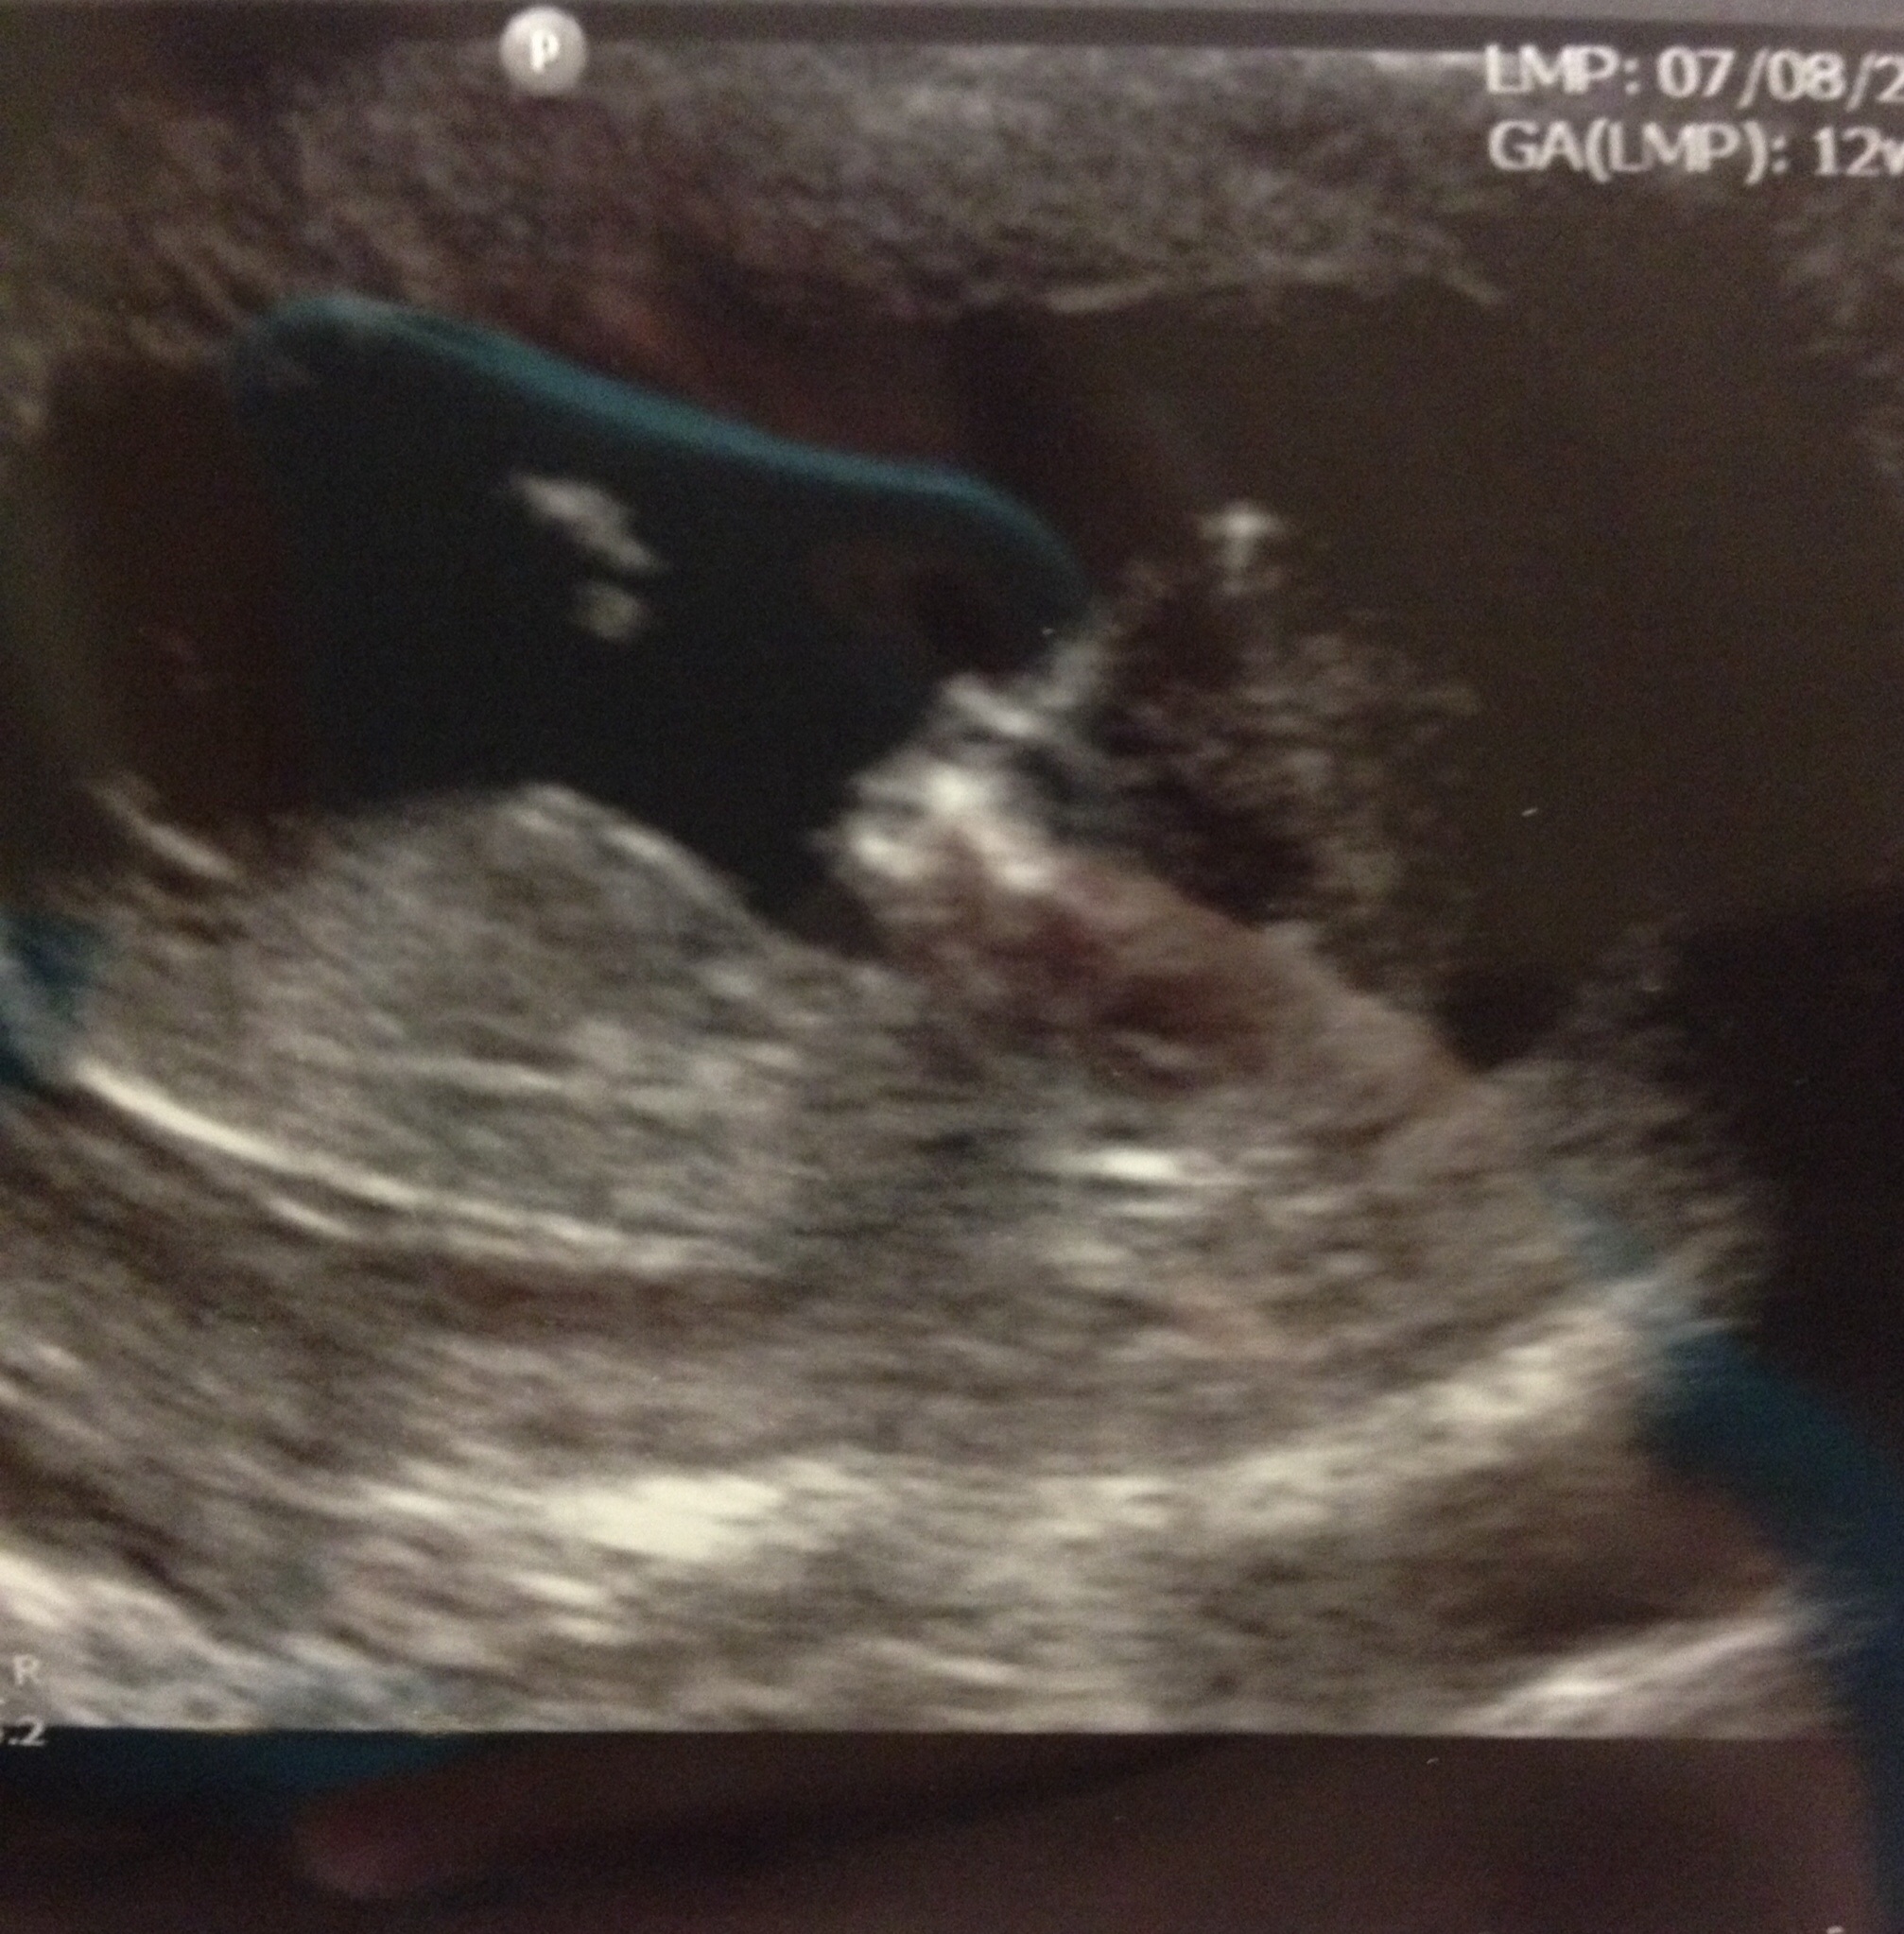

Yayyy hump day bump day!!! Been waiting since Thursday to share this photo from our NT scan! 12w2d but baby measured 12w6d! Everything looked great at the ultrasound although baby didn't want to cooperate! Will get the blood results today or tomorrow! I think the hb was 153.

I'm waiting on bloodwork now, but here's the ultrasound picture. LMP puts me at 12w1d, baby is measuring 12w3d. Heartbeat is 160-164 bpm. The blue thing is the reflection of my phone case lol.